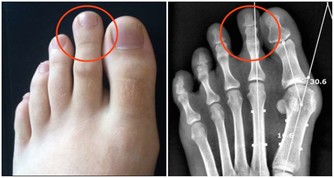

亞健康人群,往往以疲勞、睡眠紊亂、疼痛等症狀表現為主,常伴有記憶力下降、注意力不集中、思維緩慢、反應遲鈍等情況。